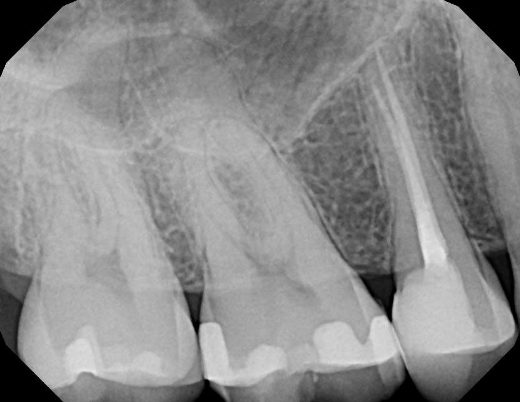

Periapical x-rays show a group of upper or lower teeth so as to better examine the root, crown and supporting bone structure of the teeth.